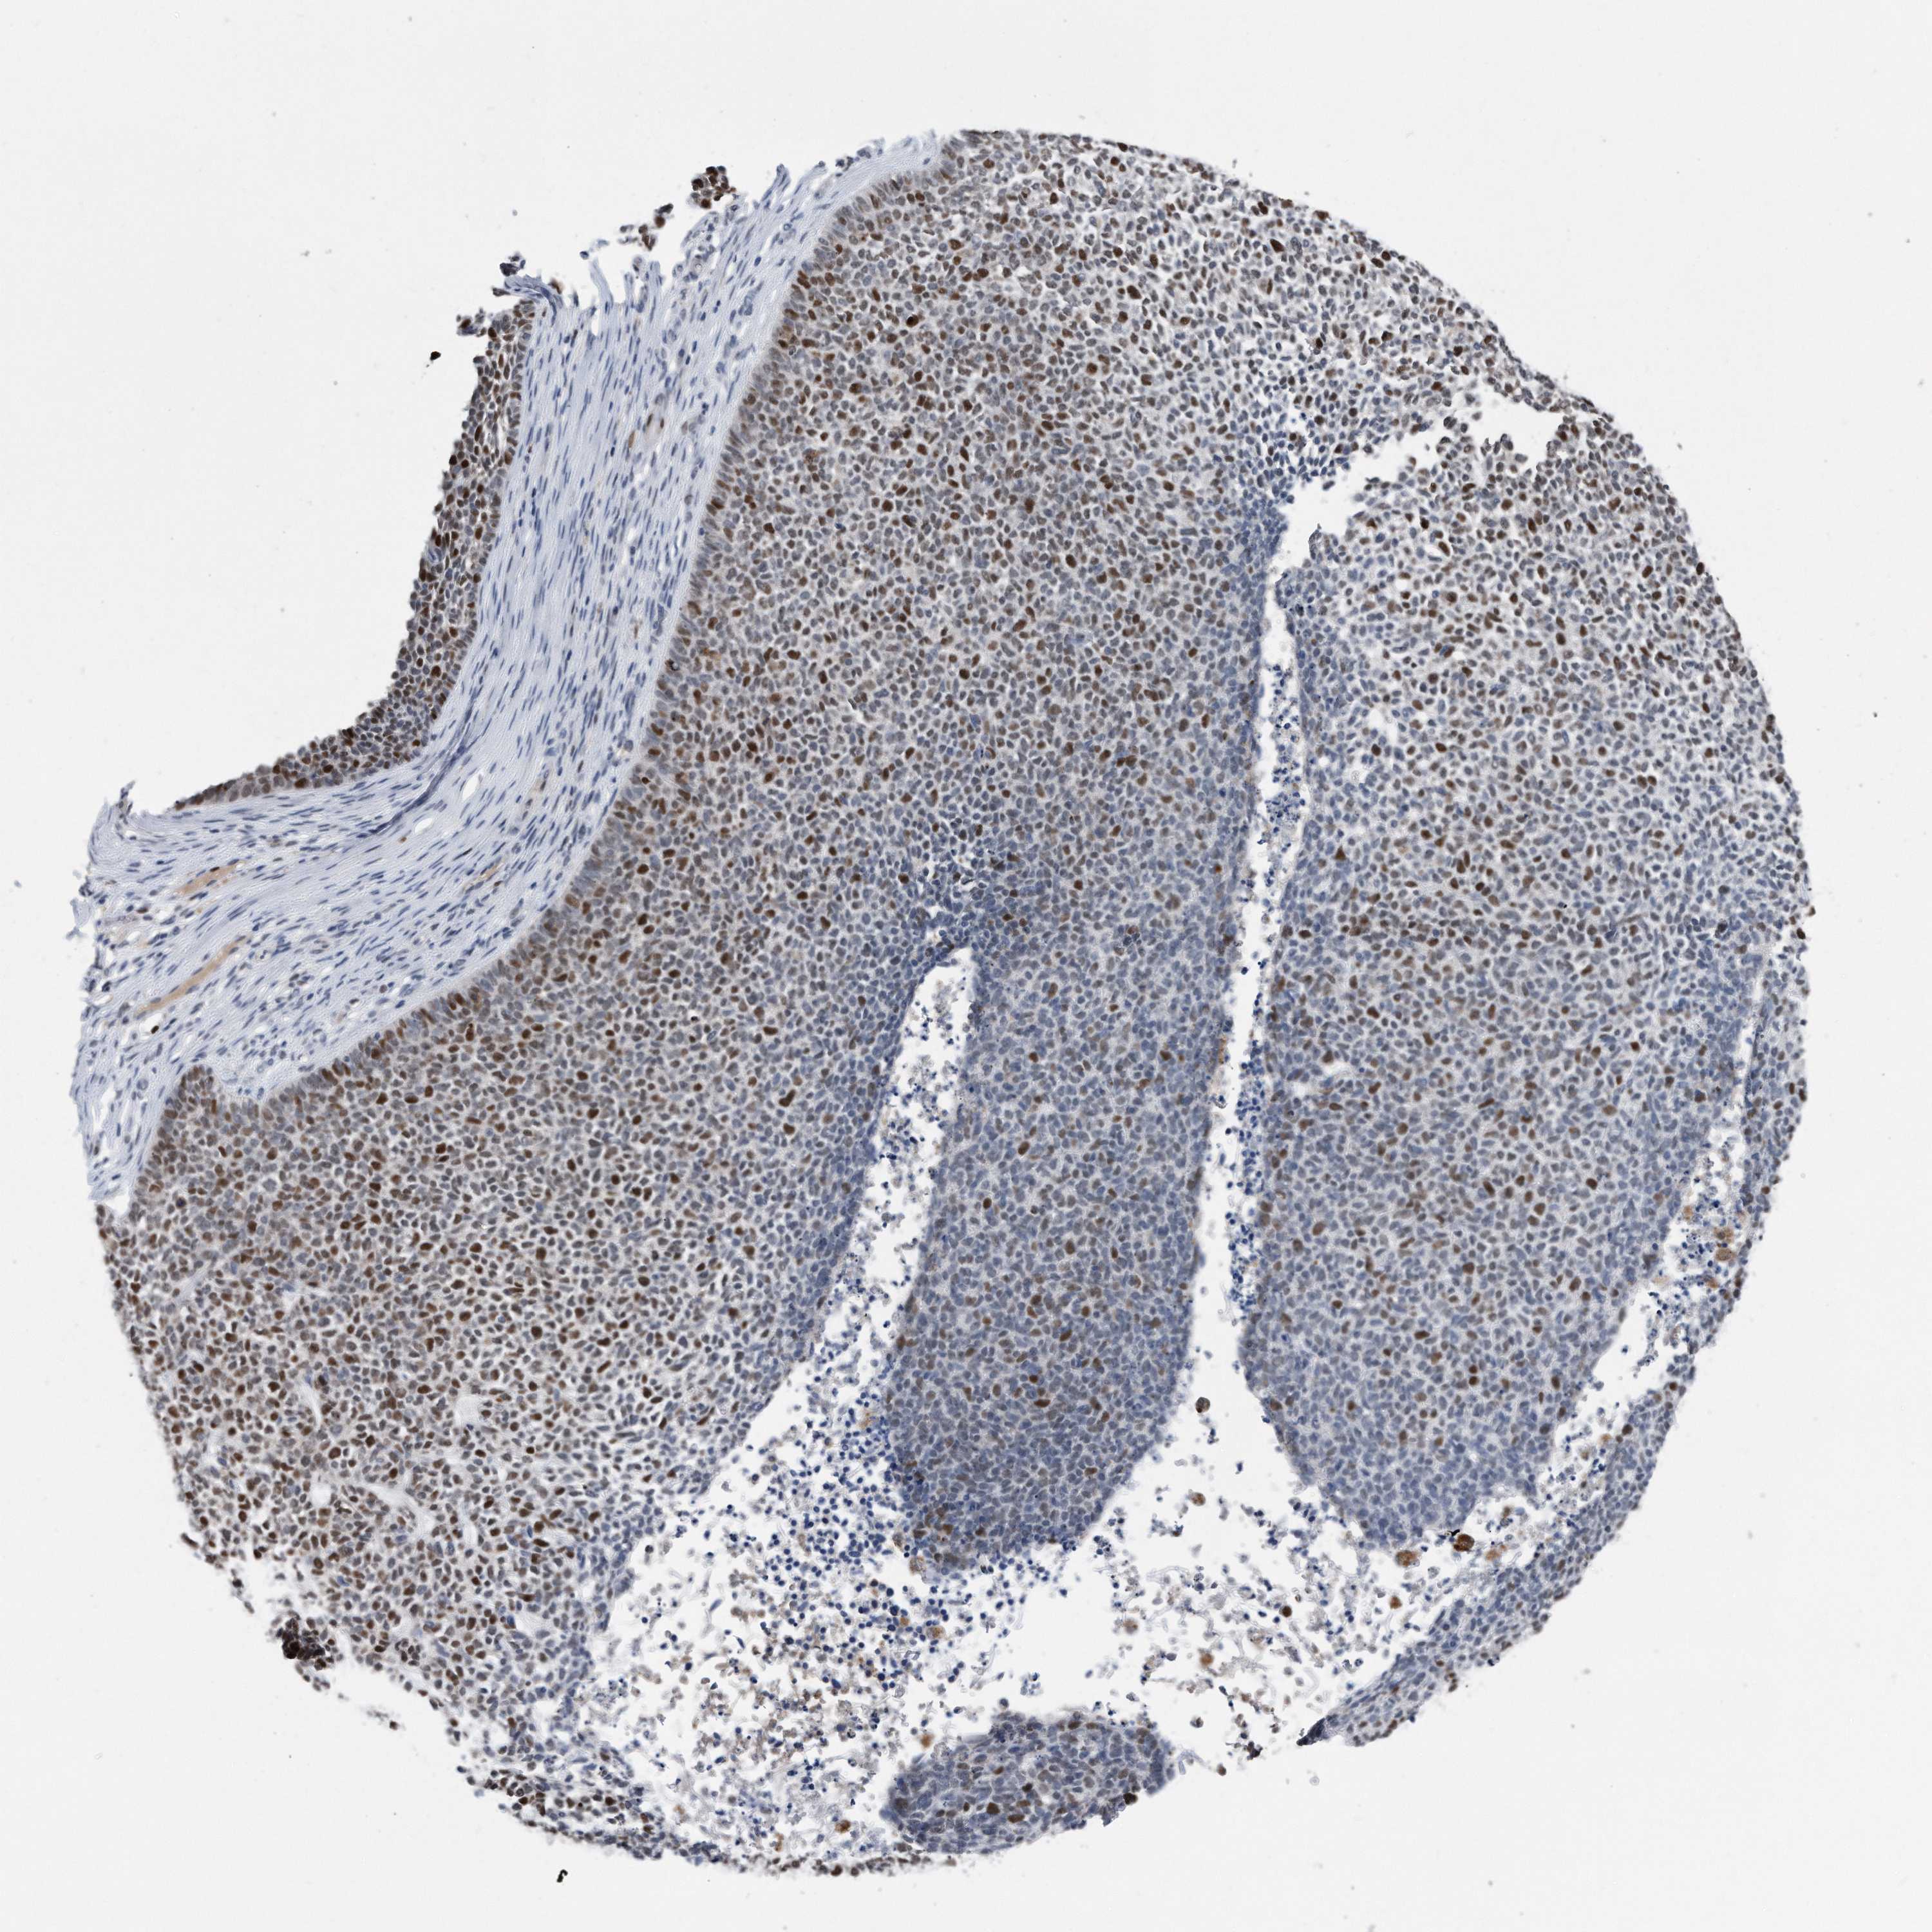

CANCER SKIN CANCER Show tissue menu

Basal cell and squamous cell cancer

SKIN CANCER - Protein expressioni

A mouse-over function shows sample information and annotation data. Click on an image to view it in a full screen mode. Samples can be filtered based on level of antibody staining by selecting one or several of the following categories: high, medium, low and not detected. The assay and annotation is described here.

Each image is clickable and will lead to virtual microscopy that enables deeper exploration of all samples and also displays staining intensity scores, fraction scores and subcellular localization as well as patient and tissue information for each sample.

HPA030521

HPA030522

HPA030523

CAB000148

CAB080240

CAB080241

CAB080242

Staining

High

Medium

Low

Not detected

Intensity

Strong

Moderate

Weak

Negative

Quantity

>75%

75%-25%

<25%

None

Location

Nuclear

Cytoplasmic/membranous

Cytoplasmic/membranous,nuclear

Basal cell carcinoma

Squamous cell carcinoma, NOS

Squamous cell carcinoma, metastatic, NOS